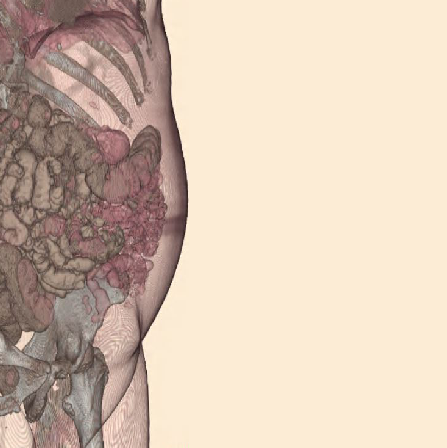

Illustrations for clear understanding

Real scan images